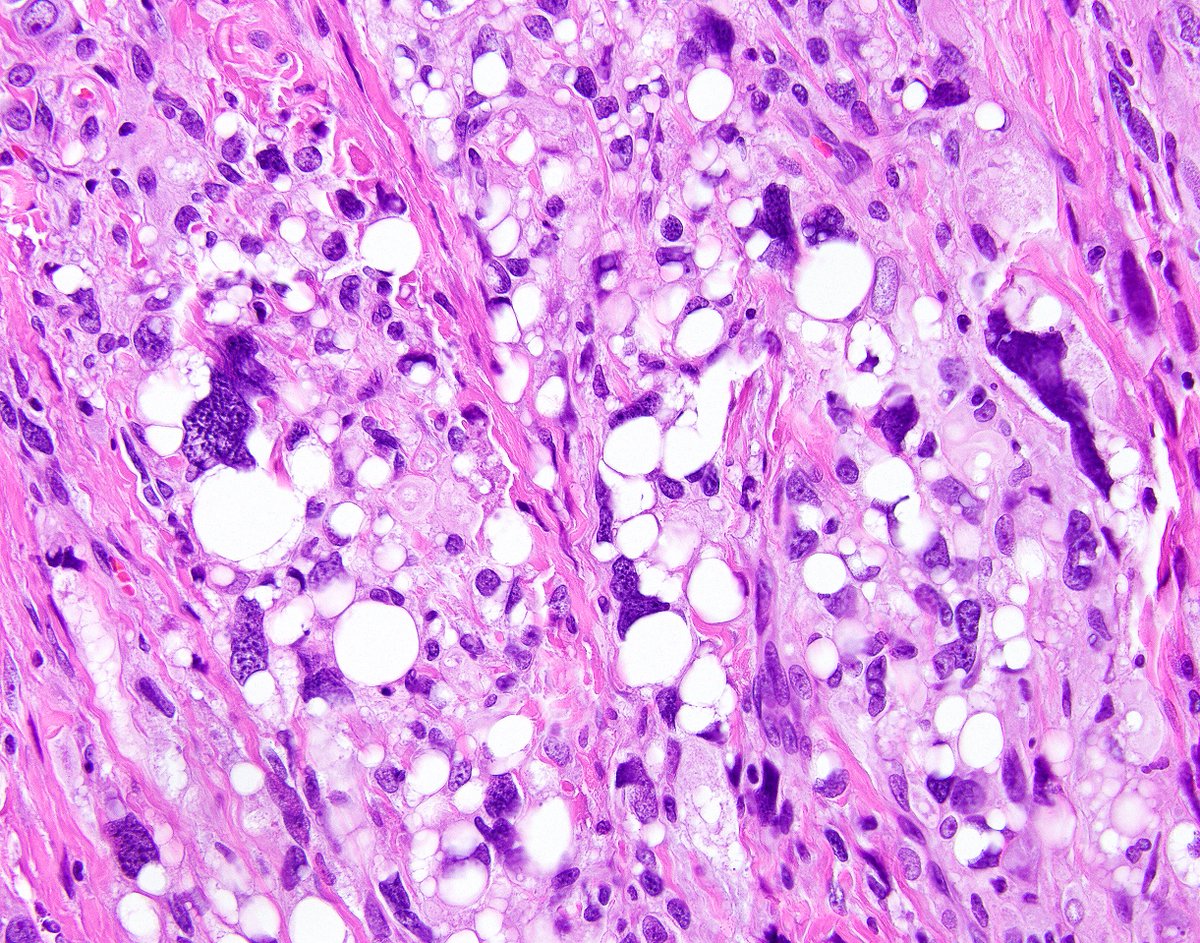

Brave New World of Breast Pathology 🧑🏫

HER2 interpretation is increasingly complex—with evolving definitions come real challenges, especially reproducibility. We’ll cover navigating HER2-low & ultralow in a clinically meaningful way.